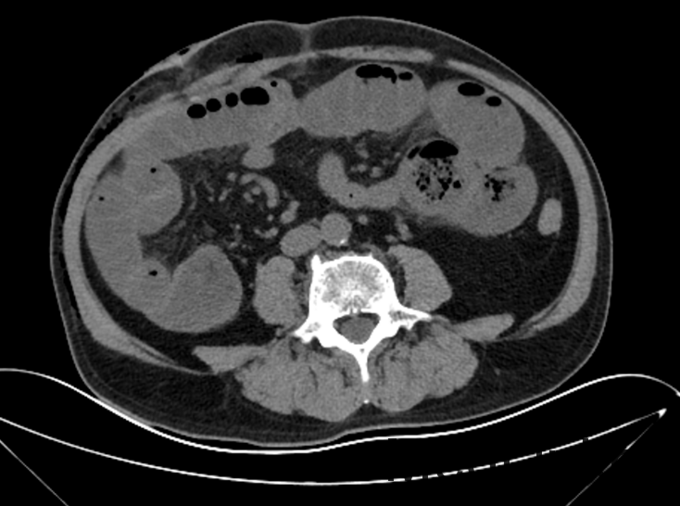

查体:P:79次/min BP 105/67mmhg SPO2 98% T36.8℃,全腹膨隆,无胃型肠型及蠕动波,脐周轻压痛,无反跳痛及肌紧张,未及包块,移动性浊音阴性,肠音消失。 辅助检查:腹部CT:右半侧泌尿系切除术后改变,肠梗阻(如图)

诊断:腹腔镜右半侧泌尿系切除术术后,炎性肠梗阻? 治疗:由泌尿外科转入我科后予抗炎,胃肠减压,抑酸抑酶,全肠外营养,腹部理疗等治疗近两周,无任何缓解迹象,后请中医科配制泻下类的中药服用1周仍无效。目前已是术后35天,肠音依然静悄悄................